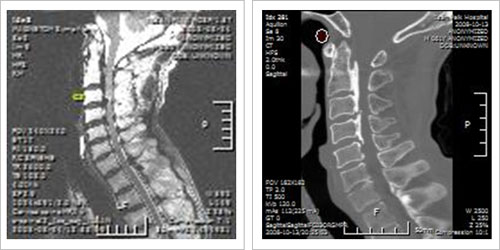

Àü¹æ°ú ÈĹæ Á¢±Ù¹ýÀ» µ¿½Ã¿¡ ÇÏ´Â ¹æ¹ý

ô¼öÁõ°ú Èĸ¸°î, °æÃßÀÇ ºñÁ¤»óÀûÀÎ Ä¿ºê(curve)°¡ ÇÔ²² ÀÖ´Â °æ¿ì°¡ ÀÖÀ¸¸ç Ä¿ºê°¡

À¯¿¬¼ºÀÌ ¾ø´Â °æ¿ì¿¡´Â µ¿½Ã¿¡ ÇØ¾ß¸¸ ÇÕ´Ï´Ù.

Ãßü ¾ÆÅ»±¸ ¹× ºÒ¾ÈÁ¤¼ºÀ» µ¿¹ÝÇÑ ½ÉÇÑ Ã´Ãß º¯¼º º¯È¿Í Àü¹æ¿¡¼ÀÇ Ã´¼ö ¾Ð¹ÚÀÌ È²»ö

ÀδëÀÇ ºñÈÄ, ÇÔ¸ô µî ÈÄ¹æ º´¸®¿Í µ¿¹ÝµÇ°Å³ª, ¼±ÃµÀûÀ¸·Î ôÃß°üÀÌ Á¼Àº °æ¿ì¿¡´Â

¾î´À ÇÑ ÂÊÀÇ ¼ö¼ú¸¸À¸·Î´Â ¿ÏÀüÇÑ Ã´¼ö °¨¾ÐÀ» ¾ò±â ¾î·Æ°í ÀüÈÄ¹æ º´Çà ¼ö¼úÀÌ ÇÊ¿äÇÕ´Ï´Ù. |